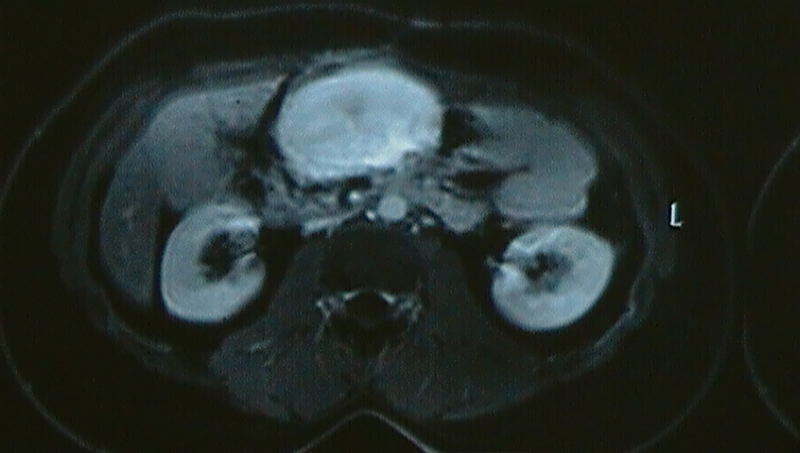

Tumors located in the central mesentery of small intestine (area between superior mesenteric artery & vein) are very difficult to operate due to the location, vascular nature, the large size they attain by the time they are diagnosed and large portion of small intestine involved. The surgery may have significant blood loss and result in removal of large segment of small intestine. The nature of these tumors could be Gastro Intestinal Stromal Tumor (GIST), Neuro Endocrine Tumor (NET), desmoid tumor, Lymphoma etcetera. These tumors may present with abdominal pain, weight loss, vomiting, abdominal distension, early satiety, intestinal obstruction, gastrointestinal bleeding (meleena – dark / blackish stools, massive bleeding per rectum, slow bleeding in stools causing anemia). Rarely they present as intestinal perforation or bleeding in the peritoneal cavity (hemoperitoneum).

Mesenteric Tumor